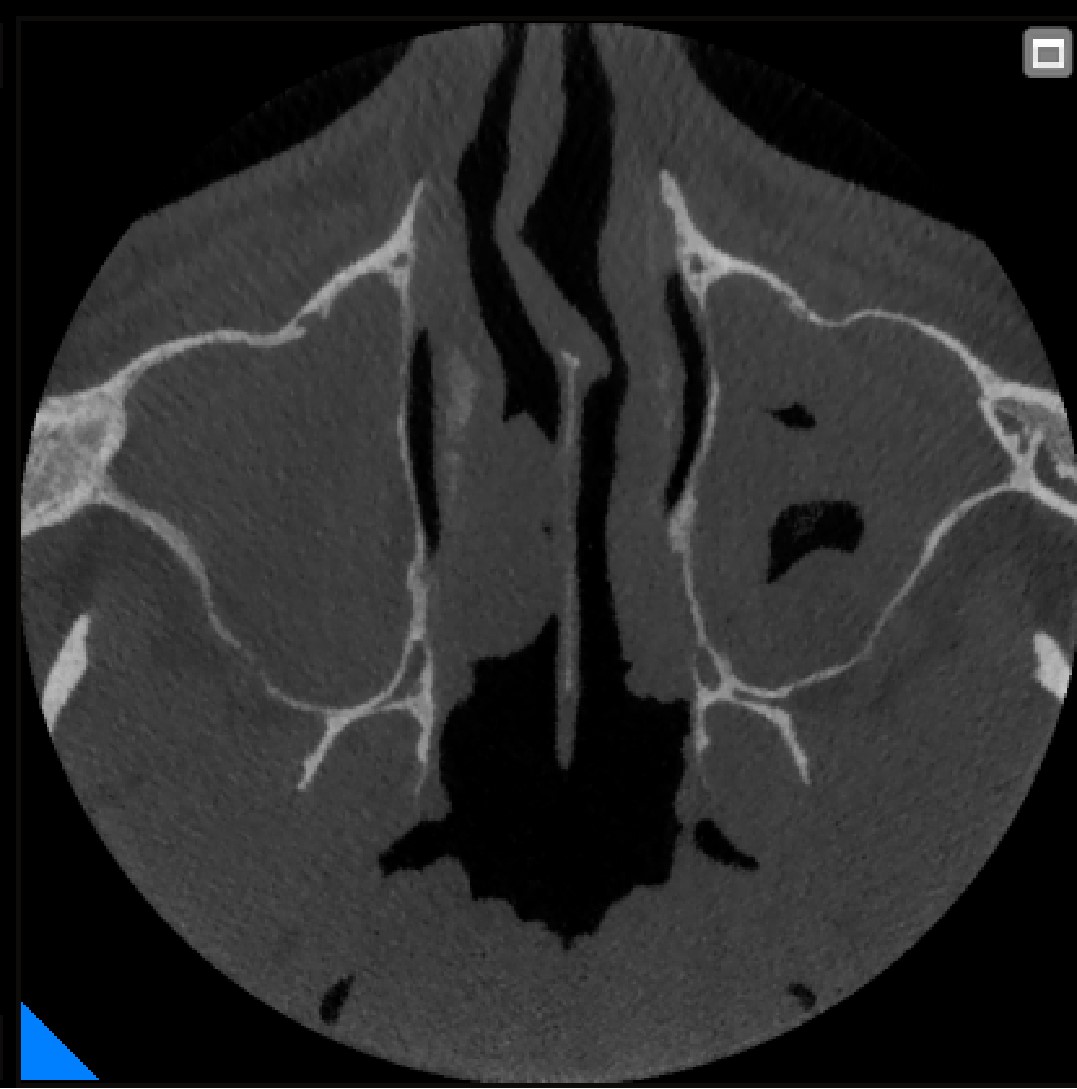

Гайморові пазухи на КТ

Інформація про форму коренів зуба, ширину та висоту кістки, розташування гайморових пазух та нижньощелепного нерву, для уникнення ризиків і ускладнень під час видалення та імплантації зубів.